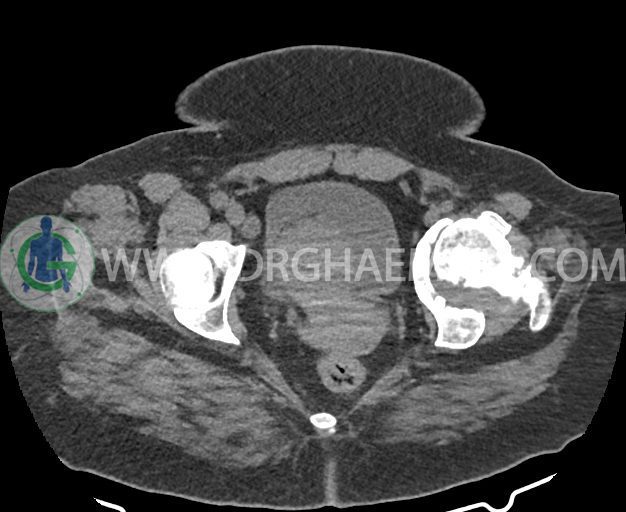

در سی تی اسکن اسپیرال شکم و لگن بدون کنتراست (مولتی دیدکتور 16 با مقاطع ظریف و بازسازی های ساژیتال و کرونال) :

-Stag horn همراه با سنگ های ریز متعدد و فراوان کنارهم در سیستم پیلوکالیسیل کلیه راست با گسترش به UPJ رویت می شود که در ادمه آن حالب غیرمتسع و بدون شواهد وجود سنگ رویت شد.

شواهد استئوآرتریت ثانویه به صورت remodeling اسکلروز و کیست های ساب کندرال و کاهش فاصله مفصلی در کمپارتمان لترال hip چپ همراه با دفورمیتی استابولوم و خصوصا سر فمور و flattening آن دیده می شود.